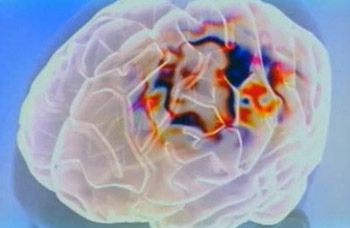

Менингит - это воспаление оболочек головного и спинного мозга. Но при этом заболевании повреждения клеток головного мозга не происходит, а сам воспалительный процесс развивается снаружи. Возбудителем менингита являются вирусы, бактерии и грибы. Причём заболеваемость не зависит от возраста, скорее она зависит от состояния организма. Например, недоношенным детям, организм которых более ослаблен, опасность менингита угрожает больше других. Также к группе риска можно отнести людей, у которых ...